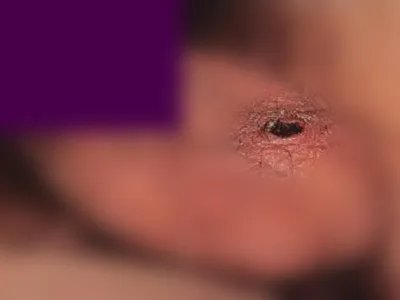

的有关信息介绍如下:概述恙虫病可出现局部焦痂,呈凹陷状,周围充血发红,触摸皮损略高于皮肤表面,多因被带有病原体的幼虫叮咬导致。恙虫病背部焦痂图

恙虫病腰部皮损表面有黑色焦痂,焦痂中间凹陷,边缘有隆起,呈“火山口”状,周围红晕明显,伴随全身发热、寒战、淋巴结肿大等表现。恙虫病臀部焦痂图

恙虫病大腿内侧有一个凹陷性的圆形黑色焦痂,焦痂边缘隆起,中间凹陷,呈“火山口”样,周围有红晕,无疼痛或瘙痒,不易被发现。恙虫病膝盖焦痂图